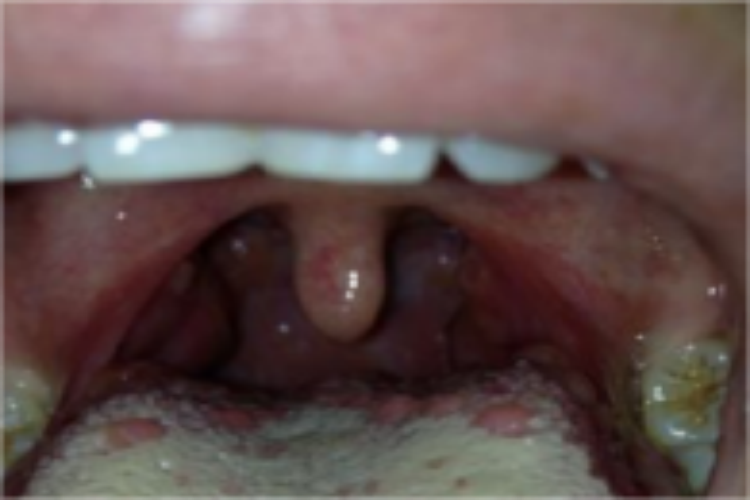

轮廓乳头:是正常解剖结构,位于舌背黏膜表面呈矮柱状的突起。是舌背乳头中体积最大者,数目最少,约有10个。它沿界沟的前方排列成一行,乳头呈柱状形态,每一个轮廓乳头间的四周均有深沟环绕。

轮廓乳头炎:位于舌后1/3,呈“人字形”排列,炎症时乳头红肿突起,疼痛不明显。也有患者无意间发现而恐惧。

舌异位甲状腺:肿块呈瘤状突起,周界清楚,表面紫蓝色,质地柔软。患者常有吞咽不畅,语言不清,呈典型的“含橄榄”语音;较大时可出现吞咽困难和不同程度的睡眠中呼吸困难等梗阻症状。